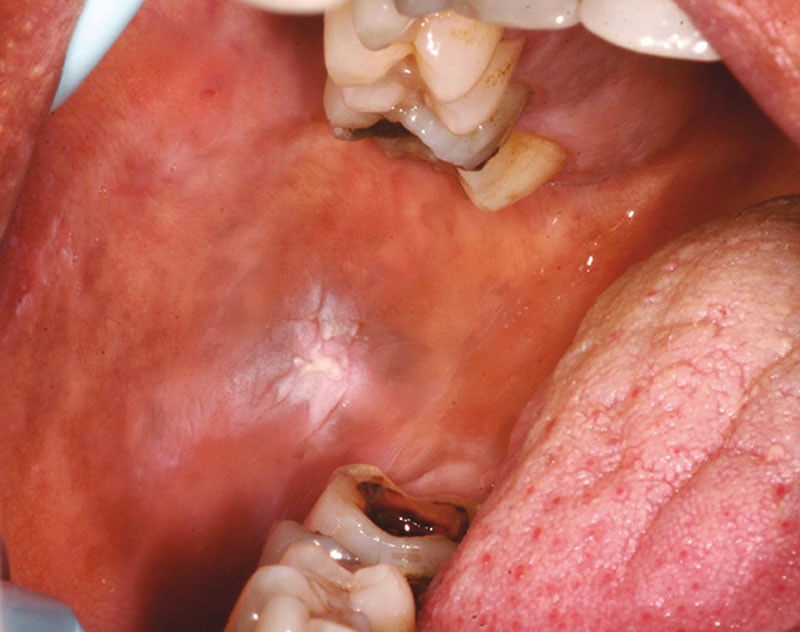

Les causes mécaniques sont les plus fréquentes. Il peut s’agir d’une dent fracturée (fig. 2) ou cariée, d’une prothèse mal adaptée, usée, d’un appareil d’orthodontie traumatique, ou de mastication sur les crêtes édentées (fig. 3).